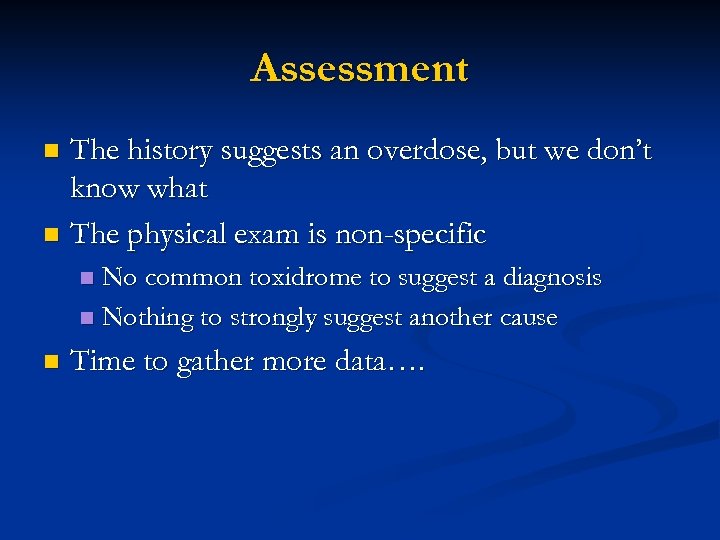

Assessment The history suggests an overdose, but we don’t know what n The physical exam is non-specific n No common toxidrome to suggest a diagnosis n Nothing to strongly suggest another cause n n Time to gather more data….

Assessment The history suggests an overdose, but we don’t know what n The physical exam is non-specific n No common toxidrome to suggest a diagnosis n Nothing to strongly suggest another cause n n Time to gather more data….